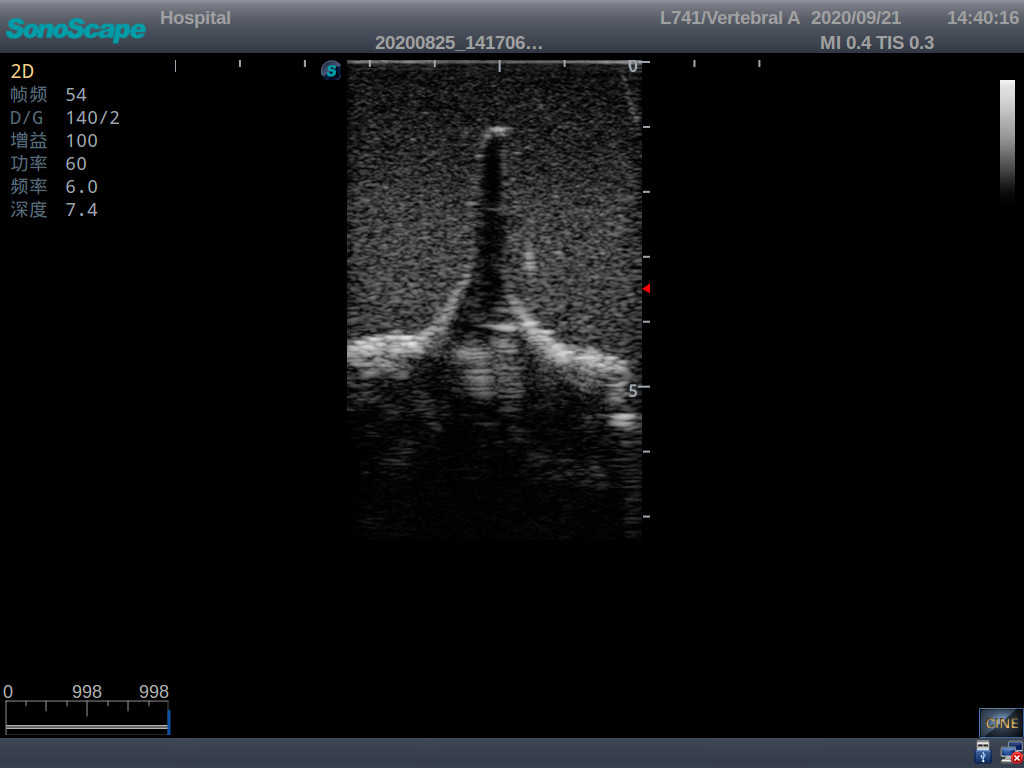

Adult Lumbar Puncture Ultrasound Training Model

Model TYE1549.2

This model is an ideal choice for ultrasound-guided adult lumbar puncture training with true-to-life skin feel and touch, accurate anatomical structures as well as real clinical ultrasound images. Realistic resistance to needle tips and correct landmarks provide excellent hands-on experience.

2)  Real clinical ultrasound images

3)  Compatible with various real ultrasound machines

1)   Ultrasound-guided lumbar puncture practice